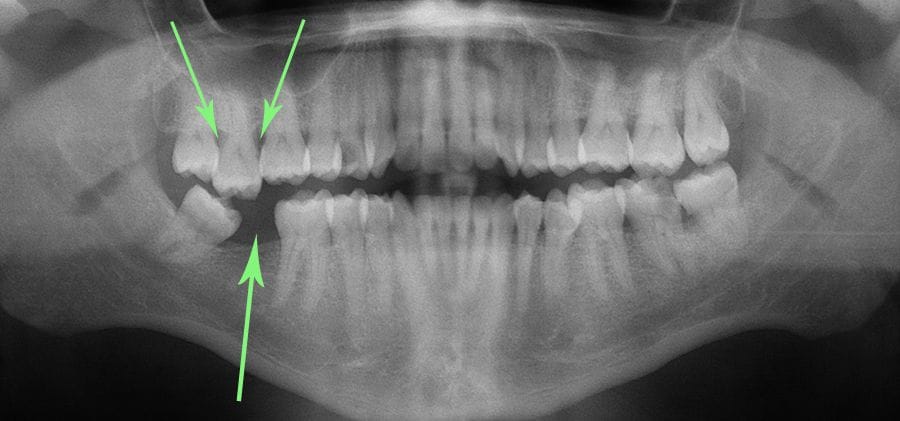

- Adjacent teeth started leaning in causing Gum problems

- Opposing tooth drifts downward

- The surrounding teeth all started moving

Overall Result: Entire area is malpositioned and more susceptible to tooth loss, gum disease and poor function.